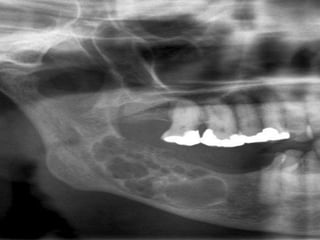

 Plain radiographs

 Panorex, dental radiographs

 CT for larger, aggressive lesions

Diagnosis  Complete history Pain, loose teeth, occlusion, swellings, dysthesias, delayed tooth eruption  Thorough physical examination  Inspection, palpation, percussion, auscultation  Plain radiographs  Panorex, dental radiographs  CT for larger, aggressive lesions